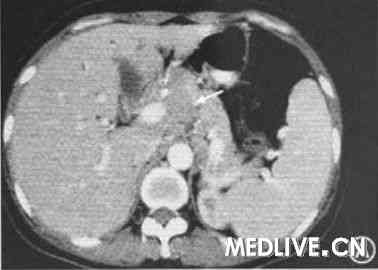

以及尿频、尿急等症状,未处理。第2天晨起体温恢复正常,当日晚发热再起,发热前有轻微寒战,体温最高达39.6℃。期间有右上腹疼痛,向后背放射。另有明显乏力、纳差、恶心,呕吐一次胃内容物。在当地医院行CT检查

,发现腹腔多发淋巴结肿大(图1A),住院诊治。给予头孢唑啉钠、氧氟沙星

,提示肝、脾肿大。为进一步诊治收住我院消化科。![]() |